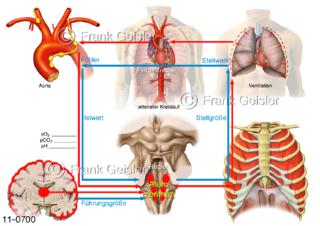

11-0700 Physiologie Atmung, Regelkreis chemische Regulation Atemregulation